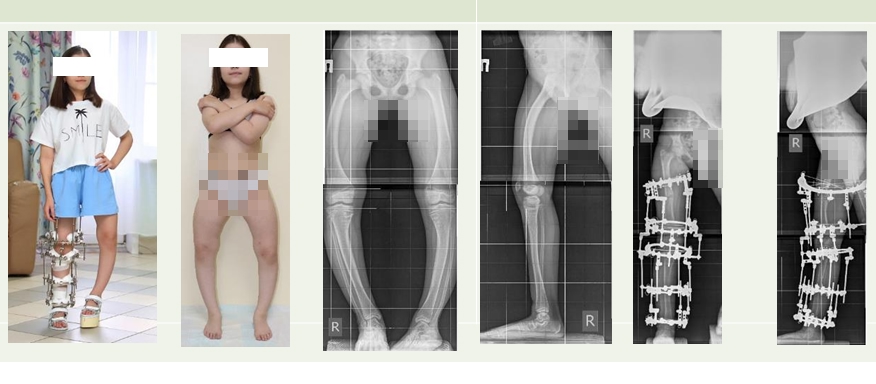

Это редкое наследственное заболевание, которое проявляется уже на первых годах жизни, но из-за схожести симптомов с другими заболеваниями часто остаётся не диагностированным. Позднее выявление приводит к тяжёлым последствиям — деформациям скелета, задержке роста, хронической боли и инвалидизации.

Характеризуется заболевание недостаточной минерализацией костной ткани в зоне ростовых пластин и другими полиорганными осложнениями на фоне нарушения реабсорбции фосфора в почках.

Многолетий опыт лечения пациентов с фосфат-диабетом имеется у отделения №17 Клиники нейроортопедии и системных заболеваний Центра Илизарова. Здесь успешно решают ортопедические проблемы, используя классику ортопедии и комбинацию методик, армируя кости данных пациентов интрамедуллярными спицами с биоактивным покрытием.

- При этом заболевании самые сложные деформации. Потому что они многоплоскостные, на всех сегментах. Кости становятся рыхлыми, вымывается фосфор, появляются множественные зоны переломов. Мы стараемся применять при лечении данных пациентов персонифицированный подход, используем самые эффективные методики, - рассказала Анна Аранович, профессор, д.м.н.

- Х-сцепленный гипофосфатемический рахит - тяжелейшее заболевание, при котором без лечения высок риск летальных исходов, однако при грамотном и своевременном подходе, в котором эффективно сочетаются хирургическое и консервативное лечение, а в некоторых случаях только таргетная терапия, заболевание проходит спокойно, - пояснила врач-вертебролог Центра Илизарова, к.м.н. Полина Очирова.